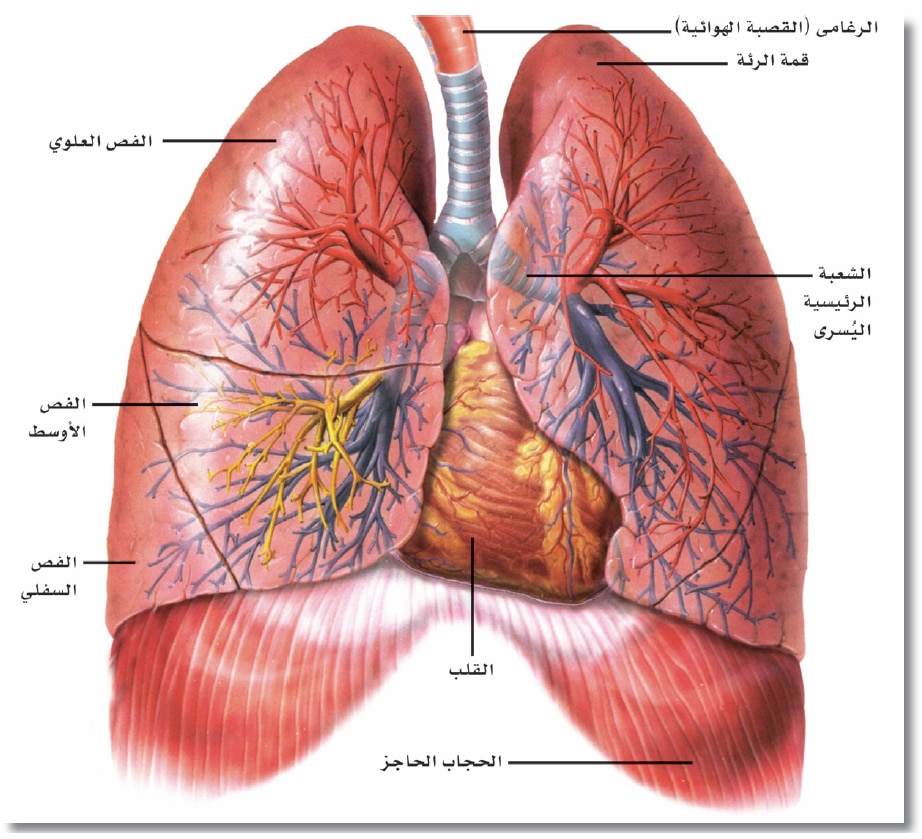

قصبة هوائية ويكيبيديا

-%D9%88%D8%B5%D9%88%D8%B1%D8%A9-%D8%AB%D9%84%D8%A7%D8%AB%D9%8A%D8%A9-%D8%A7%D9%84%D8%A3%D8%A8%D8%B9%D8%A7%D8%AF-%D9%84%D9%84%D8%B1%D8%A6%D8%AA%D9%8A%D9%86-%D9%88%D8%A7%D9%84%D9%82%D8%B5%D8%A8%D8%A9-%D8%A7%D9%84%D9%87%D9%88%D8%A7%D8%A6%D9%8A%D8%A9.jpg)

جهاز تنفسي ويكيبيديا

وظائف الرئتين الرئة البشرية البنية الوظيفة الدواء 2020

موضوعات علمية من الخطب الموضوع 280 الرئتين موسوعة النابلسي للعلوم الإسلامية

أين تقع الرئتين في جسم الإنسان موضوع